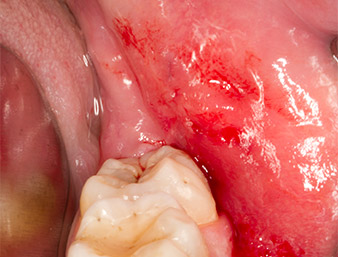

After block and local anaesthesia, the operating site was opened up and the soft tissue exposed for buccal retromolar access (Fig. 3).

sulcular incision

Fig. 3: The sulcular incision begins in mid-tooth 36 (LL6), with distal extension on the ascending ramus.